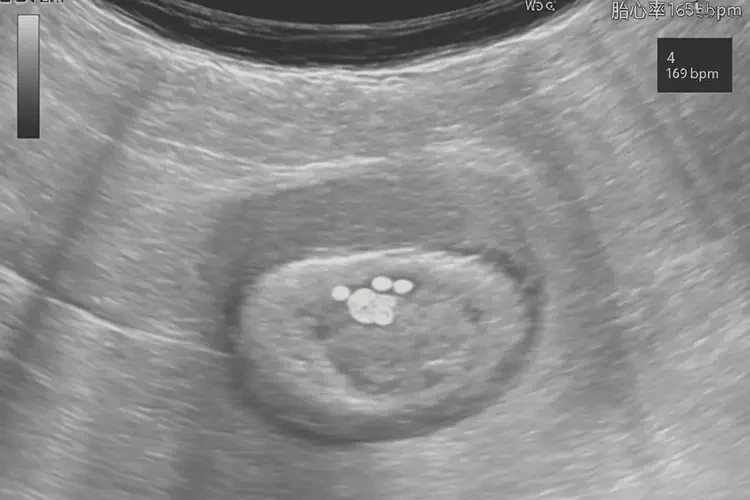

胎心率165次/分钟

怀孕4周时,胎心率达到165次/分钟是正常现象。胎心率是指胎儿心脏每分钟跳动的次数,通常在怀孕早期,胎心率会相对较高。以下是关于怀孕4周胎心率的详细解释:

早期胎心率:在怀孕4-8周,胎心率通常在150-180次/分钟之间。165次/分钟的胎心率在这个范围内,属于正常情况。